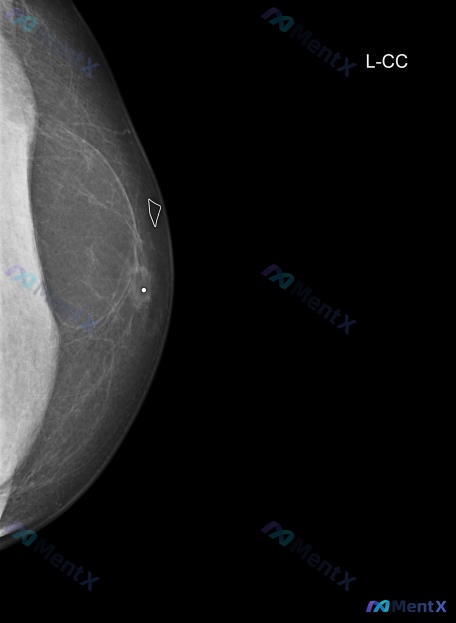

整理了一个男性乳腺肿块的病例资料,第一眼有点小陷阱: - 患者:49岁男性 - 主诉:左侧乳腺可触及肿块 - 钼靶(L-CC位): - 脂肪型乳腺(ACR a型) - 外侧象限见边界清楚的圆形/卵圆形高密度结节 - 结节中心似乎有高密度钙化或金属标记物(白色圆点) - 周围有纤维组织牵拉,但整体边缘...